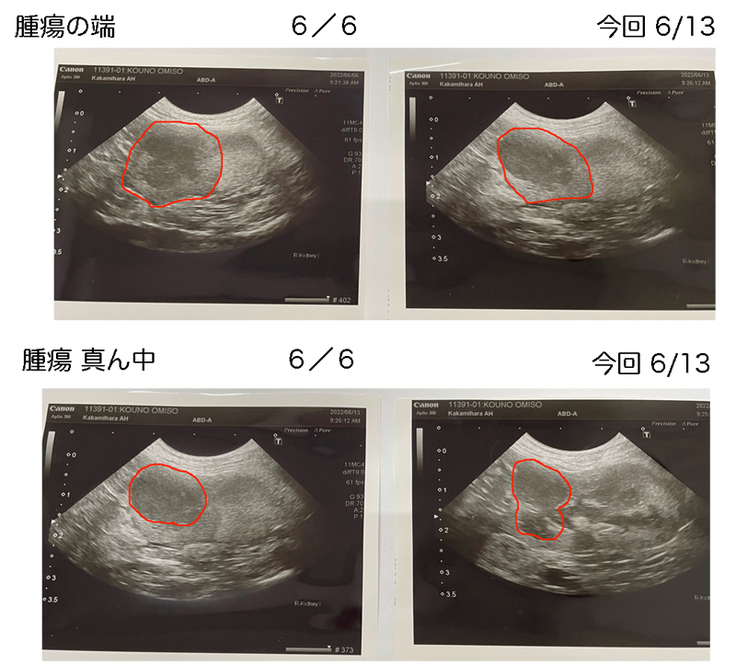

腫瘍のエコー検査では、腫瘍の端の画像では、それ程変化は無いようですが、腫瘍の真ん中画像では、下部に黒く腫瘍の膨らみがみられました。

やはり、強固な腫瘍のようです。